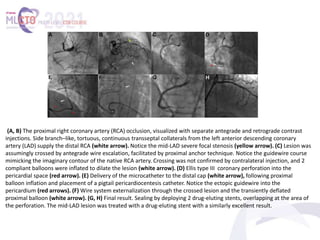

(A, B) The proximal right coronary artery (RCA) occlusion, visualized with separate antegrade and retrograde contrast

injections. Side branch–like, tortuous, continuous transseptal collaterals from the left anterior descending coronary

artery (LAD) supply the distal RCA (white arrow). Notice the mid-LAD severe focal stenosis (yellow arrow). (C) Lesion was

assumingly crossed by antegrade wire escalation, facilitated by proximal anchor technique. Notice the guidewire course

mimicking the imaginary contour of the native RCA artery. Crossing was not confirmed by contralateral injection, and 2

compliant balloons were inflated to dilate the lesion (white arrow). (D) Ellis type III coronary perforation into the

pericardial space (red arrow). (E) Delivery of the microcatheter to the distal cap (white arrow), following proximal

balloon inflation and placement of a pigtail pericardiocentesis catheter. Notice the ectopic guidewire into the

pericardium (red arrows). (F) Wire system externalization through the crossed lesion and the transiently deflated

proximal balloon (white arrow). (G, H) Final result. Sealing by deploying 2 drug-eluting stents, overlapping at the area of

the perforation. The mid-LAD lesion was treated with a drug-eluting stent with a similarly excellent result.

(A, B) Perforation caused by antegrade

ballooning. (C) Retrograde crossing of the lesion with

a guidewire away from the perforation site (true

retrograde crossing). (D) Sealing the perforation by

crushing the body of the lesion onto the vessel

walls. (E, F) An alternative scenario, where the

retrograde wire navigated the lesion through the

connection created by antegrade ballooning (reverse

controlled antegrade and retrograde subintimal

tracking technique). In this unfavorable scenario, a

covered stent would be necessary.